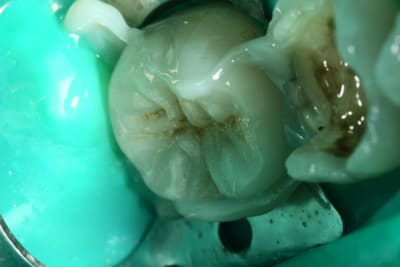

Vue l’épaisseur des parois et le fat qu'elles ont bcp travaillés avec les amalgames

> deux CR

au pire, on peut tenter deux onlays avec recouvrement desdites parois

Ouais enfin le point de contact laisse franchement à désirer, et le joint idem, et sur la 7 c'est posé au pouce et légèrement irritant pour la gencive en lingual, et enfin il en manque un peu en mésio-vestibulaire, non?

voilà la fin

Evidemment très joli boulot comme d'habitude; j'aurais probablement choisi la même méthode, mais sûrement pas avec la petite touche qui rend l'intégration si parfaite...Très joli boulot d'Alapex également.